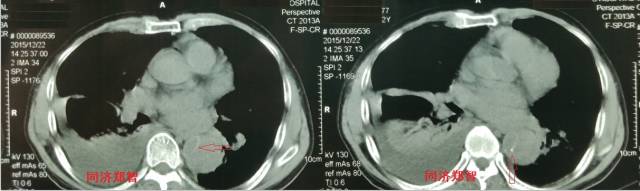

病例十

腹主动脉平扫CT提示正常外周一圈的钙化影中有内移的钙化影(红色箭头所示),CTA 证实为腹主动脉夹层。